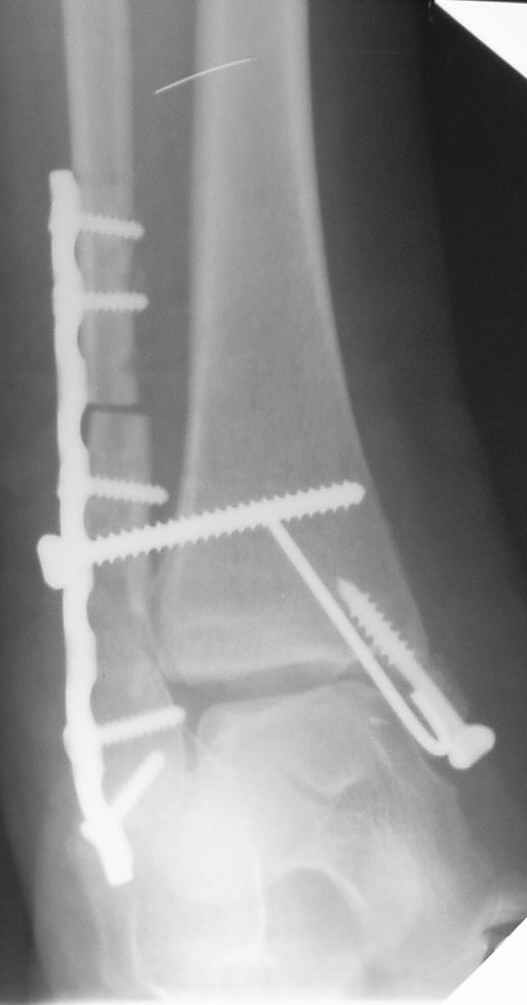

Уважаемые коллеги! Персонально, дорогой доктор Джолдас. Не знаю, почему почта к тебе не проходит - у меня почтовая программа "Bat", снимки в JPG. Выставляю через форум. 10 апреля я показывал снимки больной с застарелым переломо-вывихом голеностопного сустава. 9 июня прооперировал, снимки прилагаю. R-контроль через месяц ходьбы на костылях, все стоит также. Разрешил частичную (20кг) нагрузку на ногу, пока жалоб нет. Ход операции - сагиттальная остеотомия по линии неправильно сросшегося перелома малоберцовой кости, остеотомия с формированием внутренней лодыжки, попытка вправления подвывиха неудачна из-за того, что "не хватало" длины малоберцовой. Остеотомия малоберцовой кости выше синдесмоза. Остеосинтез.

На снимках хорошо сохранный голеностопный сустав, подвывих устранен, суставная щель одинаково прослеживается со всех сторон, небольшая нехватка длины малоберцовой и немного выступает пластина, а так в целом репозиция и фиксация удалось. Иногда, синдесмотический шуруп мы вводим немного длиннее, примерно на 3мм за медиальный кортекс, при переломе шурупа после нагрузки, шуруп легко удаляется с медиальной стороны. После 6 недель в гипсе можно разрешить нагрузку.